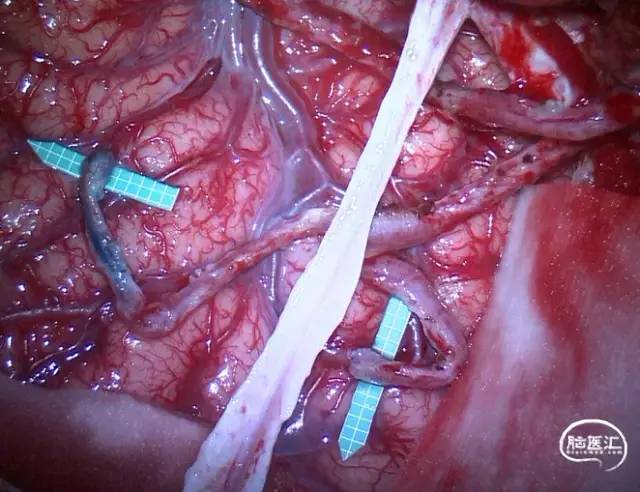

2021年,佟志勇等[17]回顾了2019-2020年5例STA-MCA/ACA序贯双吻合术(SDA)治疗MMD的病例,其中3例为STA-MCA-STA-ACA序贯双吻合术(世界首例)。STA中段和M4侧侧吻合,STA末端的额上回A5端侧吻合。使用单定点连续缝合法。术中测量STA压强为74mmHg(1mmHg=0.133kPa),A5压强为28mmHg,M4压强为29mmHg,STA侧壁压强为65mmHg。术中STA的切割流量(CF)为15~36ml/min,平均(23.6±7.7ml/min;术后1周STA流量为40~125ml/min,平均(96.8±31.2)ml/min。术后1周STA血流量为术中CF的4.1倍。

2021年,余冠东和佟志勇等[18]回顾对照研究了STA-ACA和STA-MCA双吻合术(DBA)与STA-MCA双吻合术治疗MMD的疗效。纳入2017-2020年的32例ACA供血区缺血的MMD患者共计41例次手术,分别行STA-ACA和STA-MCA双吻合术联合EMS(ACA组,10例计10例次手术)(2019-2020年)和STA-MCA双吻合术联合EMS(MCA组,25例计31例次手术)。结果显示:ACA组治疗ACA供血区缺血的MMD,桥血管通畅性良好,可获得满意的长期疗效;与MCA组相比,ACA组STA的切割流量指数(CFI)值更高,而两组术后长期疗效相当。

佟志勇等自2019年1月[17,18]开始挑选STA长度理想、ACA供血区缺血的烟雾病患者行STA⁃ACA吻合术。该术式的核心为: